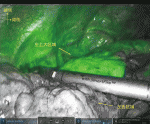

われわれは術野の固定に際しリトラクトアームを用いている.特に気管支形成術においては,気管支にかけた牽引糸を把持することで固定された良好な術野を得ることが出来る.